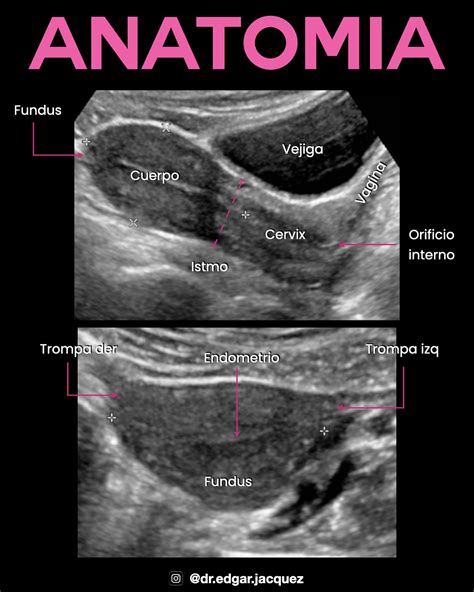

Vejiga ecografia posicion refers to the ultrasound examination of the bladder in different positions. This diagnostic tool uses high-frequency sound waves to create images of the bladder, helping healthcare providers assess its size, shape, and any abnormalities. The procedure is non-invasive and provides valuable information about the bladder's health and function.

• Positioning: The patient will be asked to lie down on an examination table. The technician will apply a gel to the lower abdomen to enhance the transmission of sound waves.

• Ultrasound Probe: A handheld device called a transducer will be moved over the abdomen to capture images of the bladder.

• Different Positions: The patient may be asked to change positions (e.g., lying on their side, standing) to get a comprehensive view of the bladder.

• Image Capture: The technician will capture images and videos of the bladder, which will be reviewed by a radiologist.

After the vejiga ecografia posicion, the images are analyzed by a radiologist who looks for various indicators: